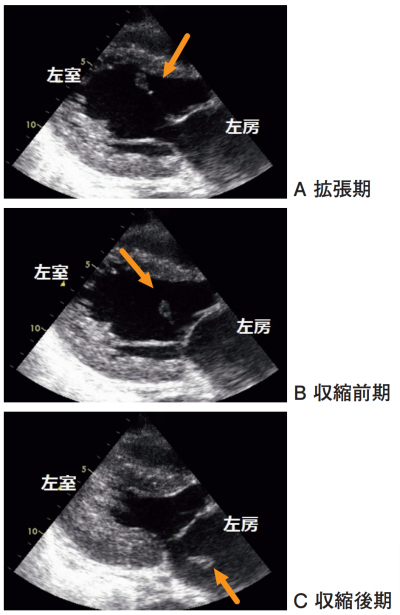

67 歳の女性。急性心筋梗塞の治療のため入院 3 日目である。 3 日前に胸痛と気分不快が出現し、緊急入院となった。同日、急性心筋梗塞の診断で冠動脈造影が施行され、引き続き、完全閉塞を認めた左前下行枝にステント留置が行われた。本日、病棟で突然、息苦しさを訴えた。収縮期血圧は 120 mmHg 台から 60 mmHg台に低下し、SpO₂ も 80 % 前後に急速に低下したため気管挿管が行われた。気管チューブからは泡沫状のピンク色の痰の流出を認めた。心エコー検査では左室駆出率は保たれていたが、左房内に逸脱する構造物を認め、カラードプラ心エコー検査で以前に認めなかった高度の僧帽弁逆流を認めた。

a. 乳頭筋断裂